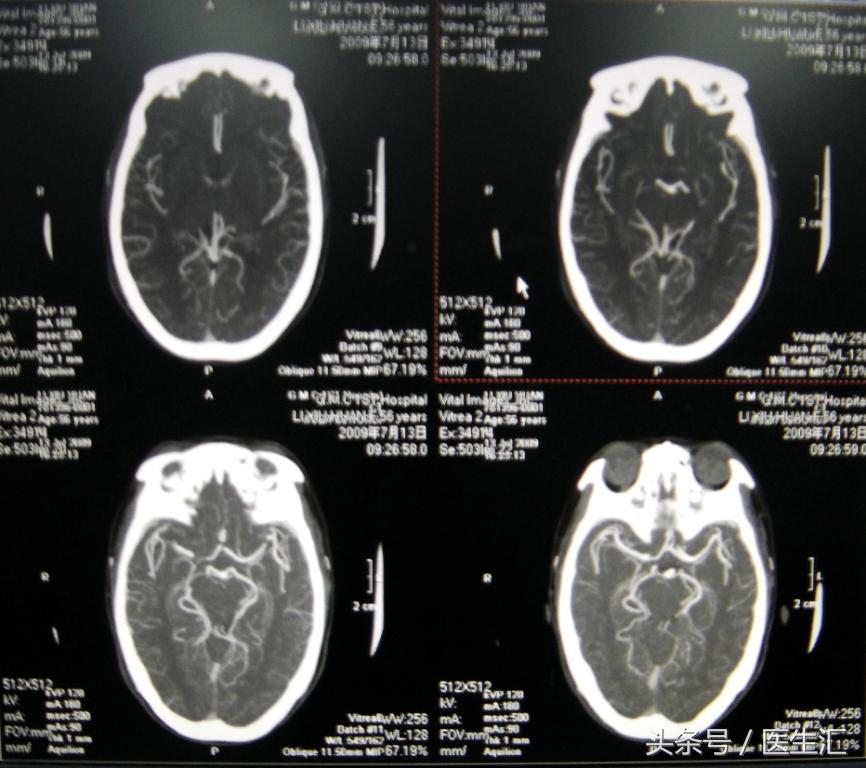

辅助检查:急诊头颅MRI(见图19)

初步诊断:基底动脉尖综合征

DSA:BA与LVA交界处斑块影,BA远端不显影,从VA缓慢注入rtPA35mg,复查BA、PCA再通(见图20)。但NIHSS评分改善不显著。